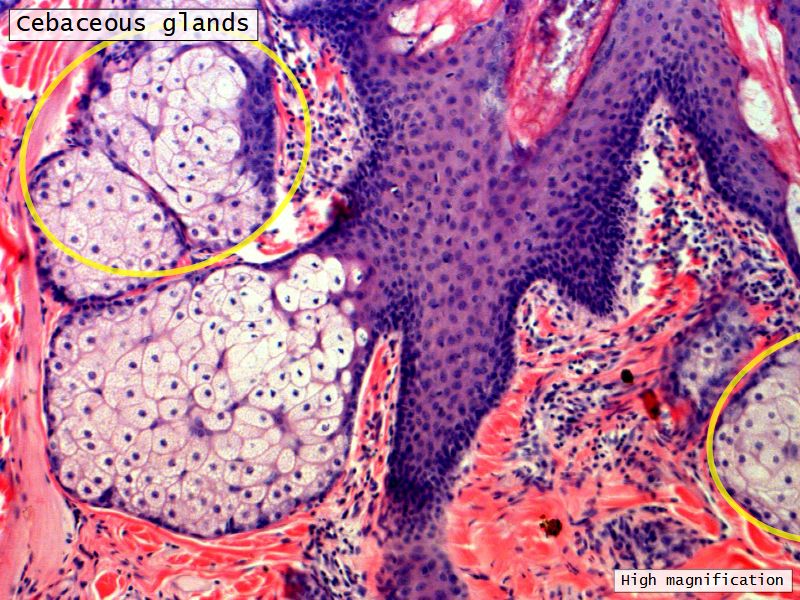

Fill in all the missing labels, and assess as you move through the slides. Answers on the down slide. It is important to do this using pen and paper, and not just glance through the images.